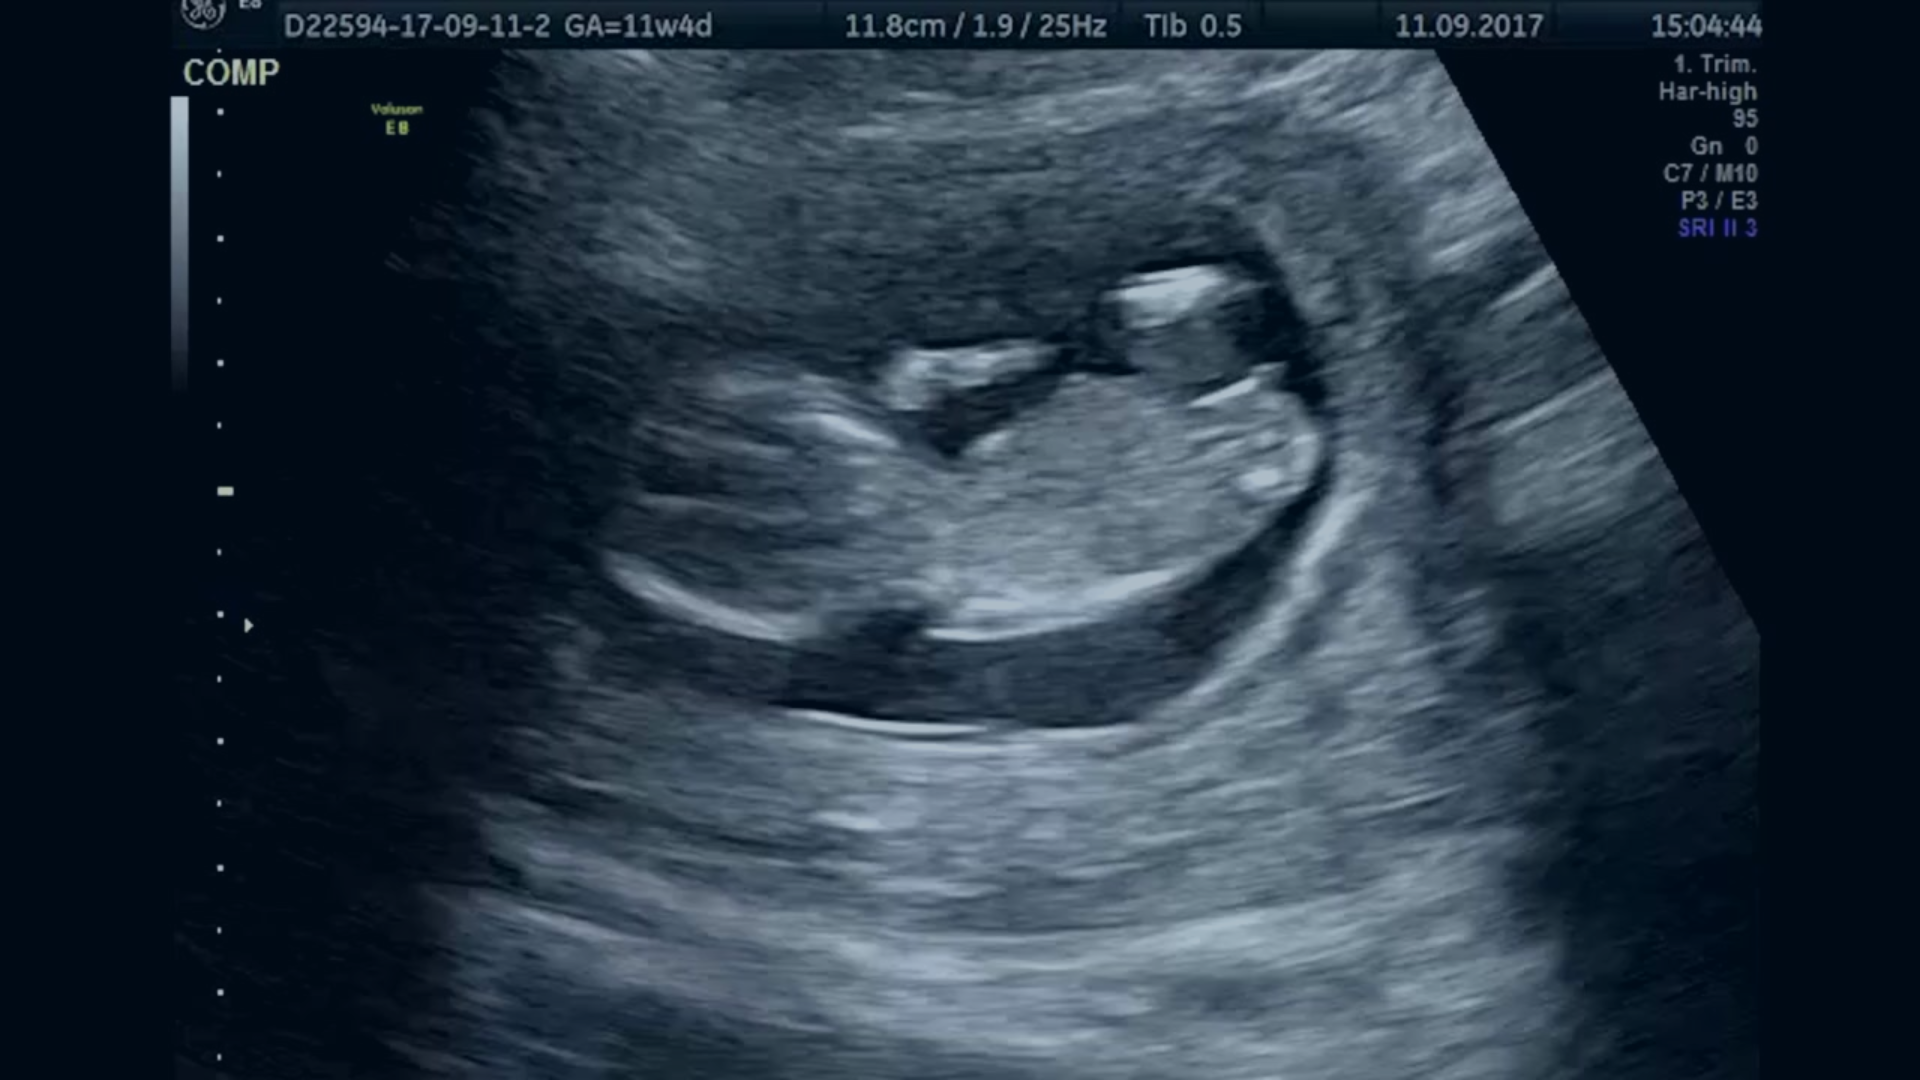

Fetal neuroimaging.

The fetal brain undergoes significant changes as a baby develops, so Oxford researchers are working to improve fetal ultrasound analysis and better standardise global measurements for fetal brain growth.

The Noble Group at the Institute of Biomedical Engineering looks at questions such as why ultrasound scanning and interpretation is so hard to learn, whether AI can simplify ultrasound and whether computers can mimic what a skilled sonographer can do.

One such collaboration proposed an automated framework for predicting age and neurodevelopmental maturation of a fetus based on 3D ultrasound brain images. This is particularly important, as accurate estimation of gestational age is essential to prenatal care.

The team, which included Professor Ana Namburete (founder of the Oxford Machine Learning in Neuroimaging Lab), Professor Alison Noble and Professor Aris Papageorghiou, developed a new feature-based model that had never before been attempted. Their analysis showed that the model did not just estimate chronological age, but also the neurodevelopmental stage of the fetus based on brain structure.